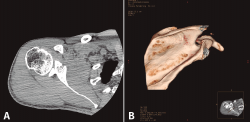

1. Fracturas articulares con desplazamiento mayor o igual a 4 mm (Figura 1). Para otros autores como Kavanagh et al.(15) sería con un desplazamiento mayor o igual a 2 mm y para Mayo et al.(11) si es mayor o igual a 5 mm.

Figura 1. Fractura articular con desplazamiento. A: fractura desplazada más de 4 mm que se trató quirúrgicamente; B: reconstrucción tridimensional de la misma fractura articular.